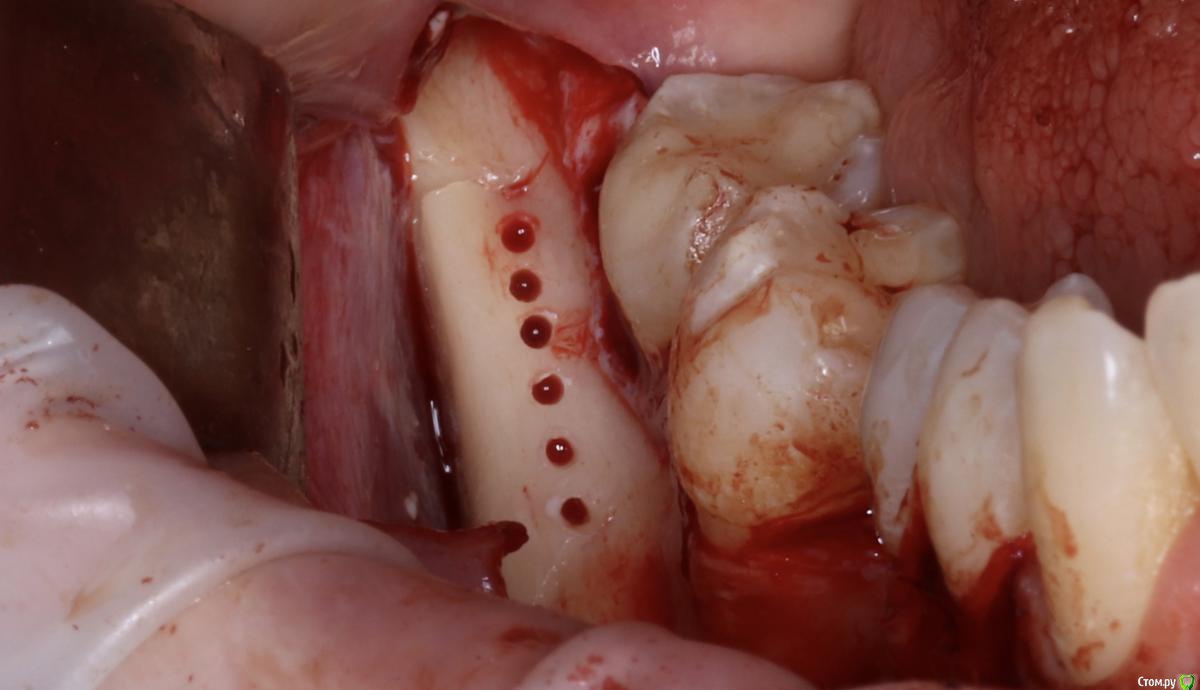

Александр07 Опубликовано 22 августа, 2020 Автор Поделиться Опубликовано 22 августа, 2020 толстый очень ламинат. а так все хорошо )Есть смысл перфорировать кортикалку, например как здесь если 1 тип кости ,, как считаете Ссылка на комментарий

АнтонТЛТ Опубликовано 22 августа, 2020 Поделиться Опубликовано 22 августа, 2020 Есть смысл перфорировать кортикалку, например как здесь если 1 тип кости ,, как считаетеАвтор методики считает, что перфорировать вообще нет никакого смысла. 3 Ссылка на комментарий